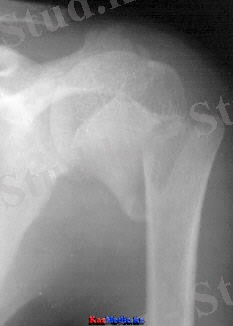

Иық сүйегінің хирургиялық мойнының сынығы